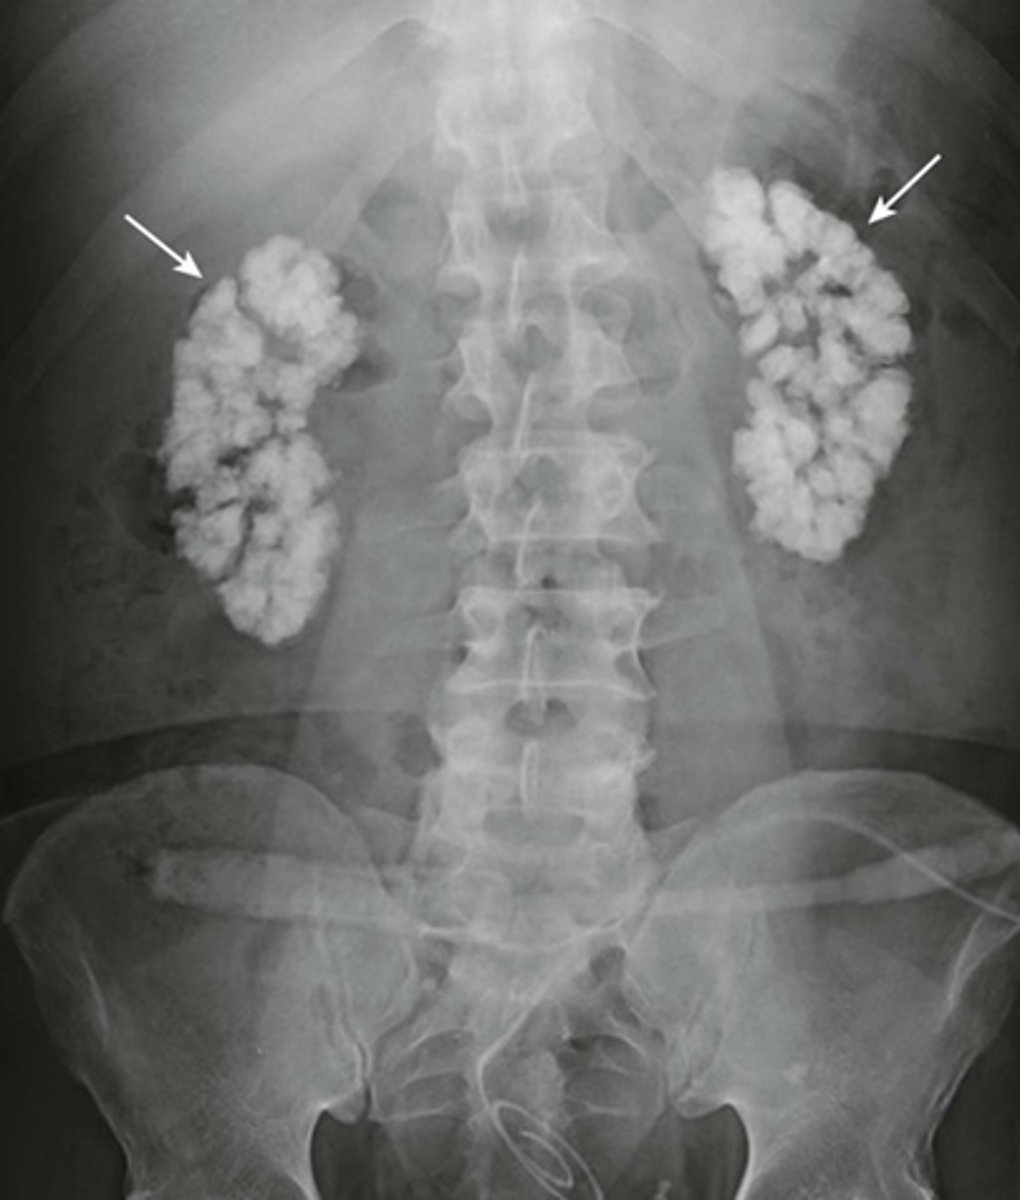

Medullary nephrocalcinosis.

WHITE ARROWS: cloudlike calcifications seen bilaterally.

suggests that these calcifications have formed within a solid organ or tumor.

The calcifications conform to the distribution of the renal collecting systems.

This is medullary nephrocalcinosis, a condition not synonymous with renal calculi because nephrocalcinosis signifies a metabolic derangement. This patient had primary hyperparathyroidism.